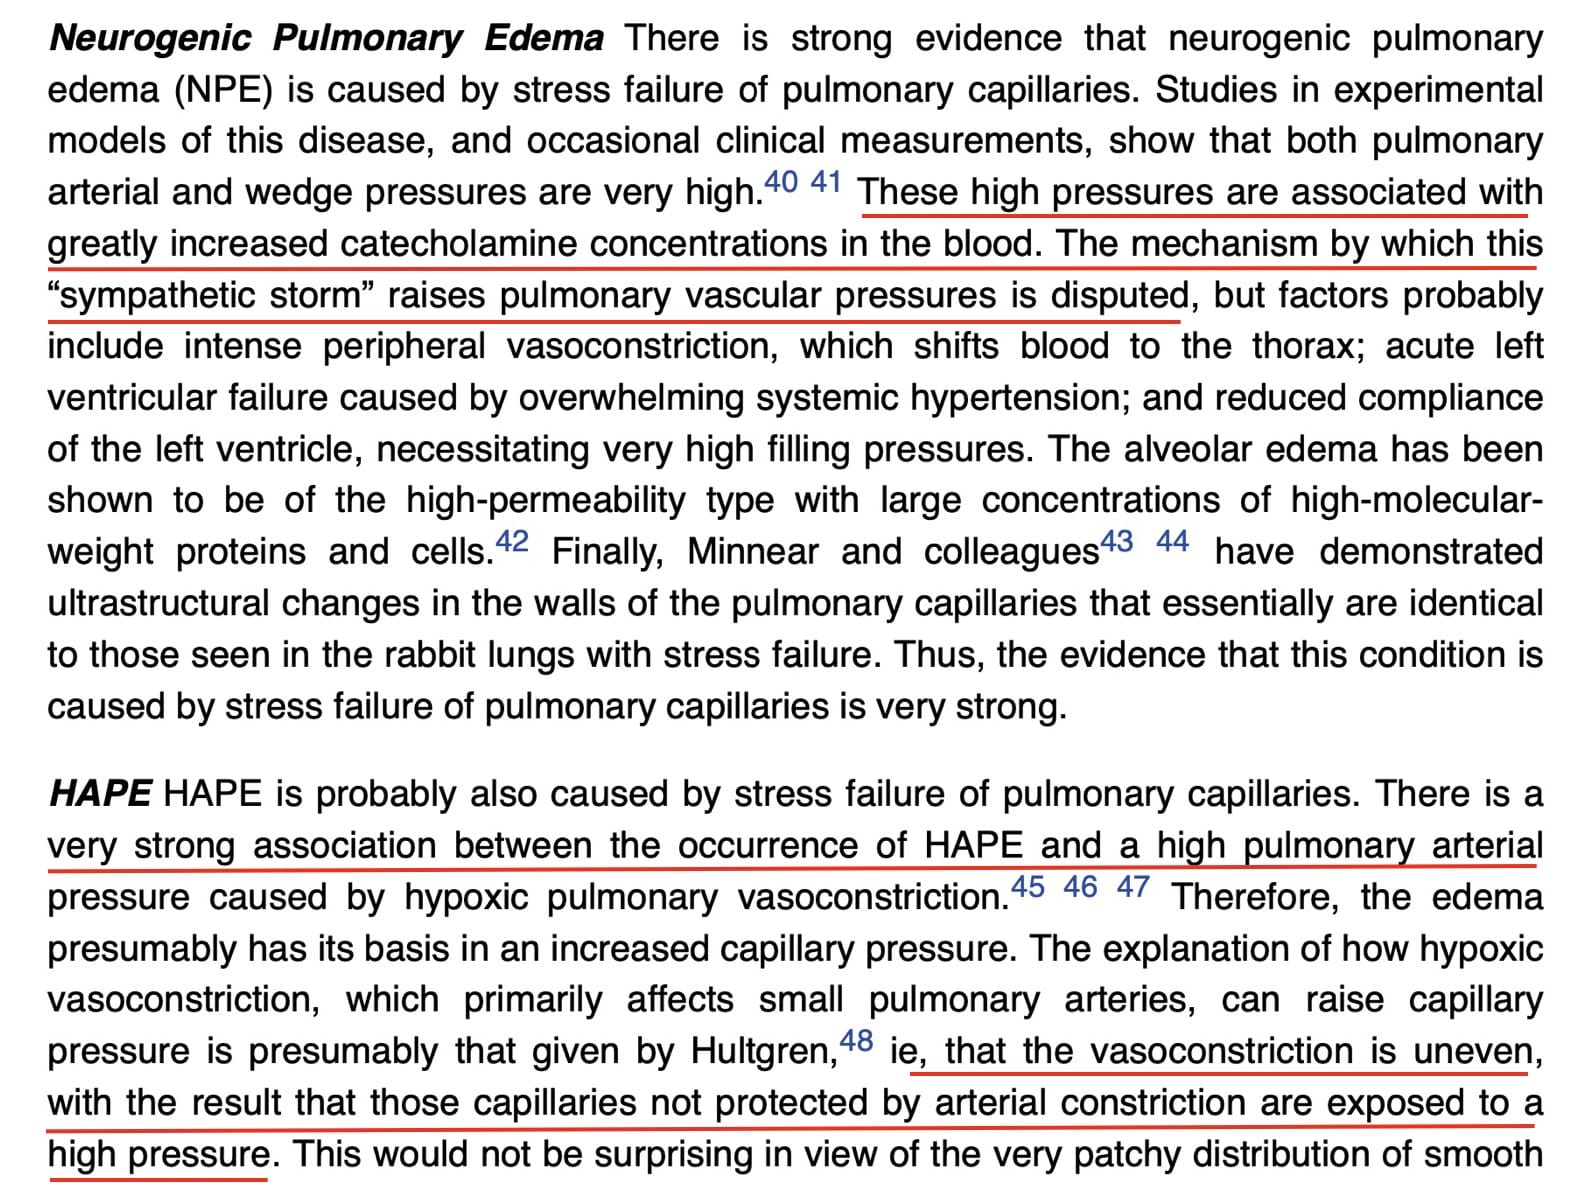

The “rules” appear to be broken. Case one represents acute lung edema from acute, severe left atrial hypertension. Yet, only minimal interstitial edema is present. Case two is high-altitude pulmonary edema; Case three is neurogenic lung edema. Case four is swimming-induced lung edema.

The explanation for these cases derives from the phenomenon of Stress Failure of Pulmonary Capillaries, a form of acute lung injury, involving the alveolar-capillary barrier. This was elucidated by John West – initially in the case of acute fatal lung edema in racehorses – and is nicely depicted in this figure from one of his articles.

Purported Mechanisms in Neurogenic and High-Altitude Pulmonary Edema